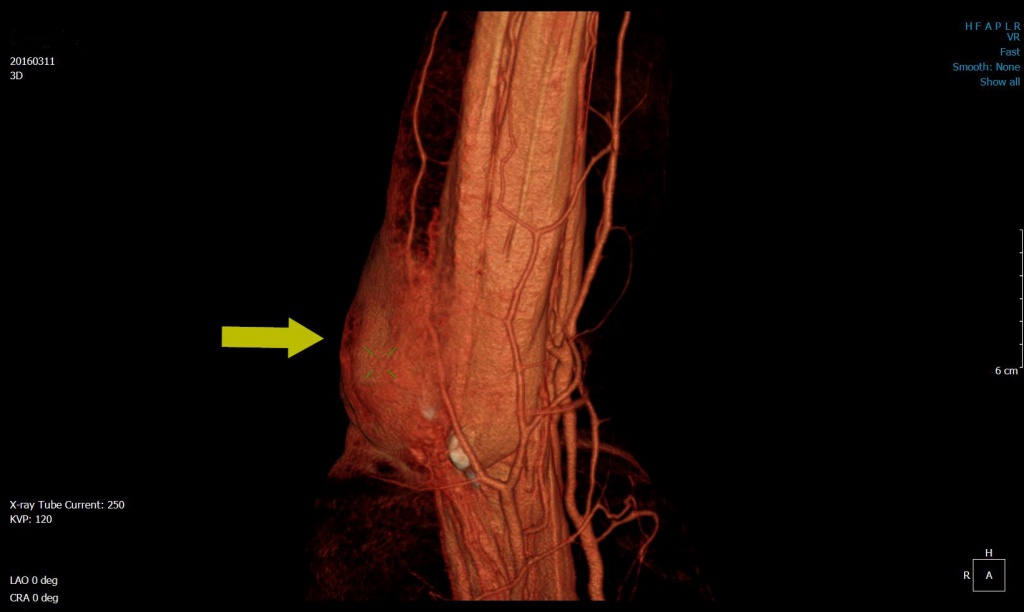

Преимущества 3D технологий при Компьютерной Томографии сосудов и мягких тканей

Нужно отметить, что КТ-диагностика ни в коей мере не претендует на исследовании мягких тканей, это прерогатива МРТ, но визуализировать мягкие ткани на КТ возмож…